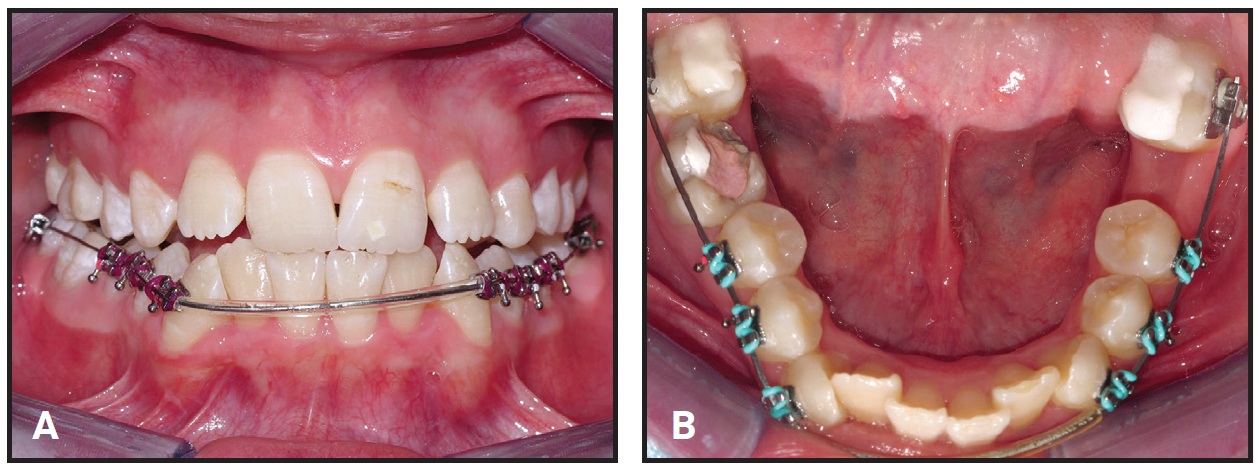

Roth-prescription .022" brackets* were bonded to the lower canines, first and second premolars, and second molars only; the lower anterior teeth were bypassed to prevent undesirable proclination (Fig. 3). The posterior teeth were discluded with glass ionomer cement to avoid occlusal interference. Leveling and alignment of the lower arch were initiated with a continuous .014" nickel titanium archwire, progressively increasing to .016" × .022" nickel titanium.

After three months of treatment, the patient was referred for surgical removal of the impacted upper canines and extraction of the lower right first molar. Lacebacks were added with ligature wire in the lower buccal segments to help relieve the crowding (Fig. 4).

Fig. 3 Lower canines, first and second premolars, and second molars bonded, with anterior teeth bypassed to prevent proclination. B. Bite raised to avoid occlusal interference.

Fig. 4 After surgical removal of impacted upper canines and extraction of lower right first molar, lacebacks added in lower buccal segments to help relieve crowding.